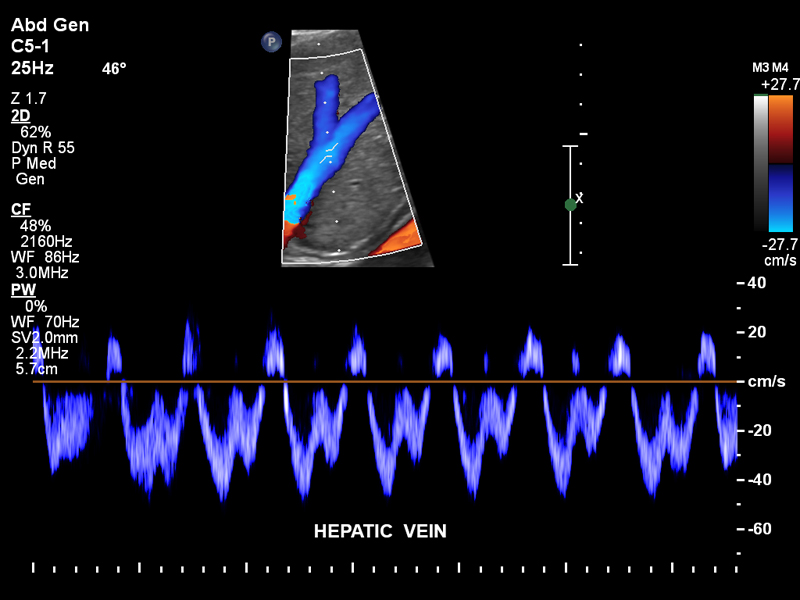

Печеночная вена, С5-1